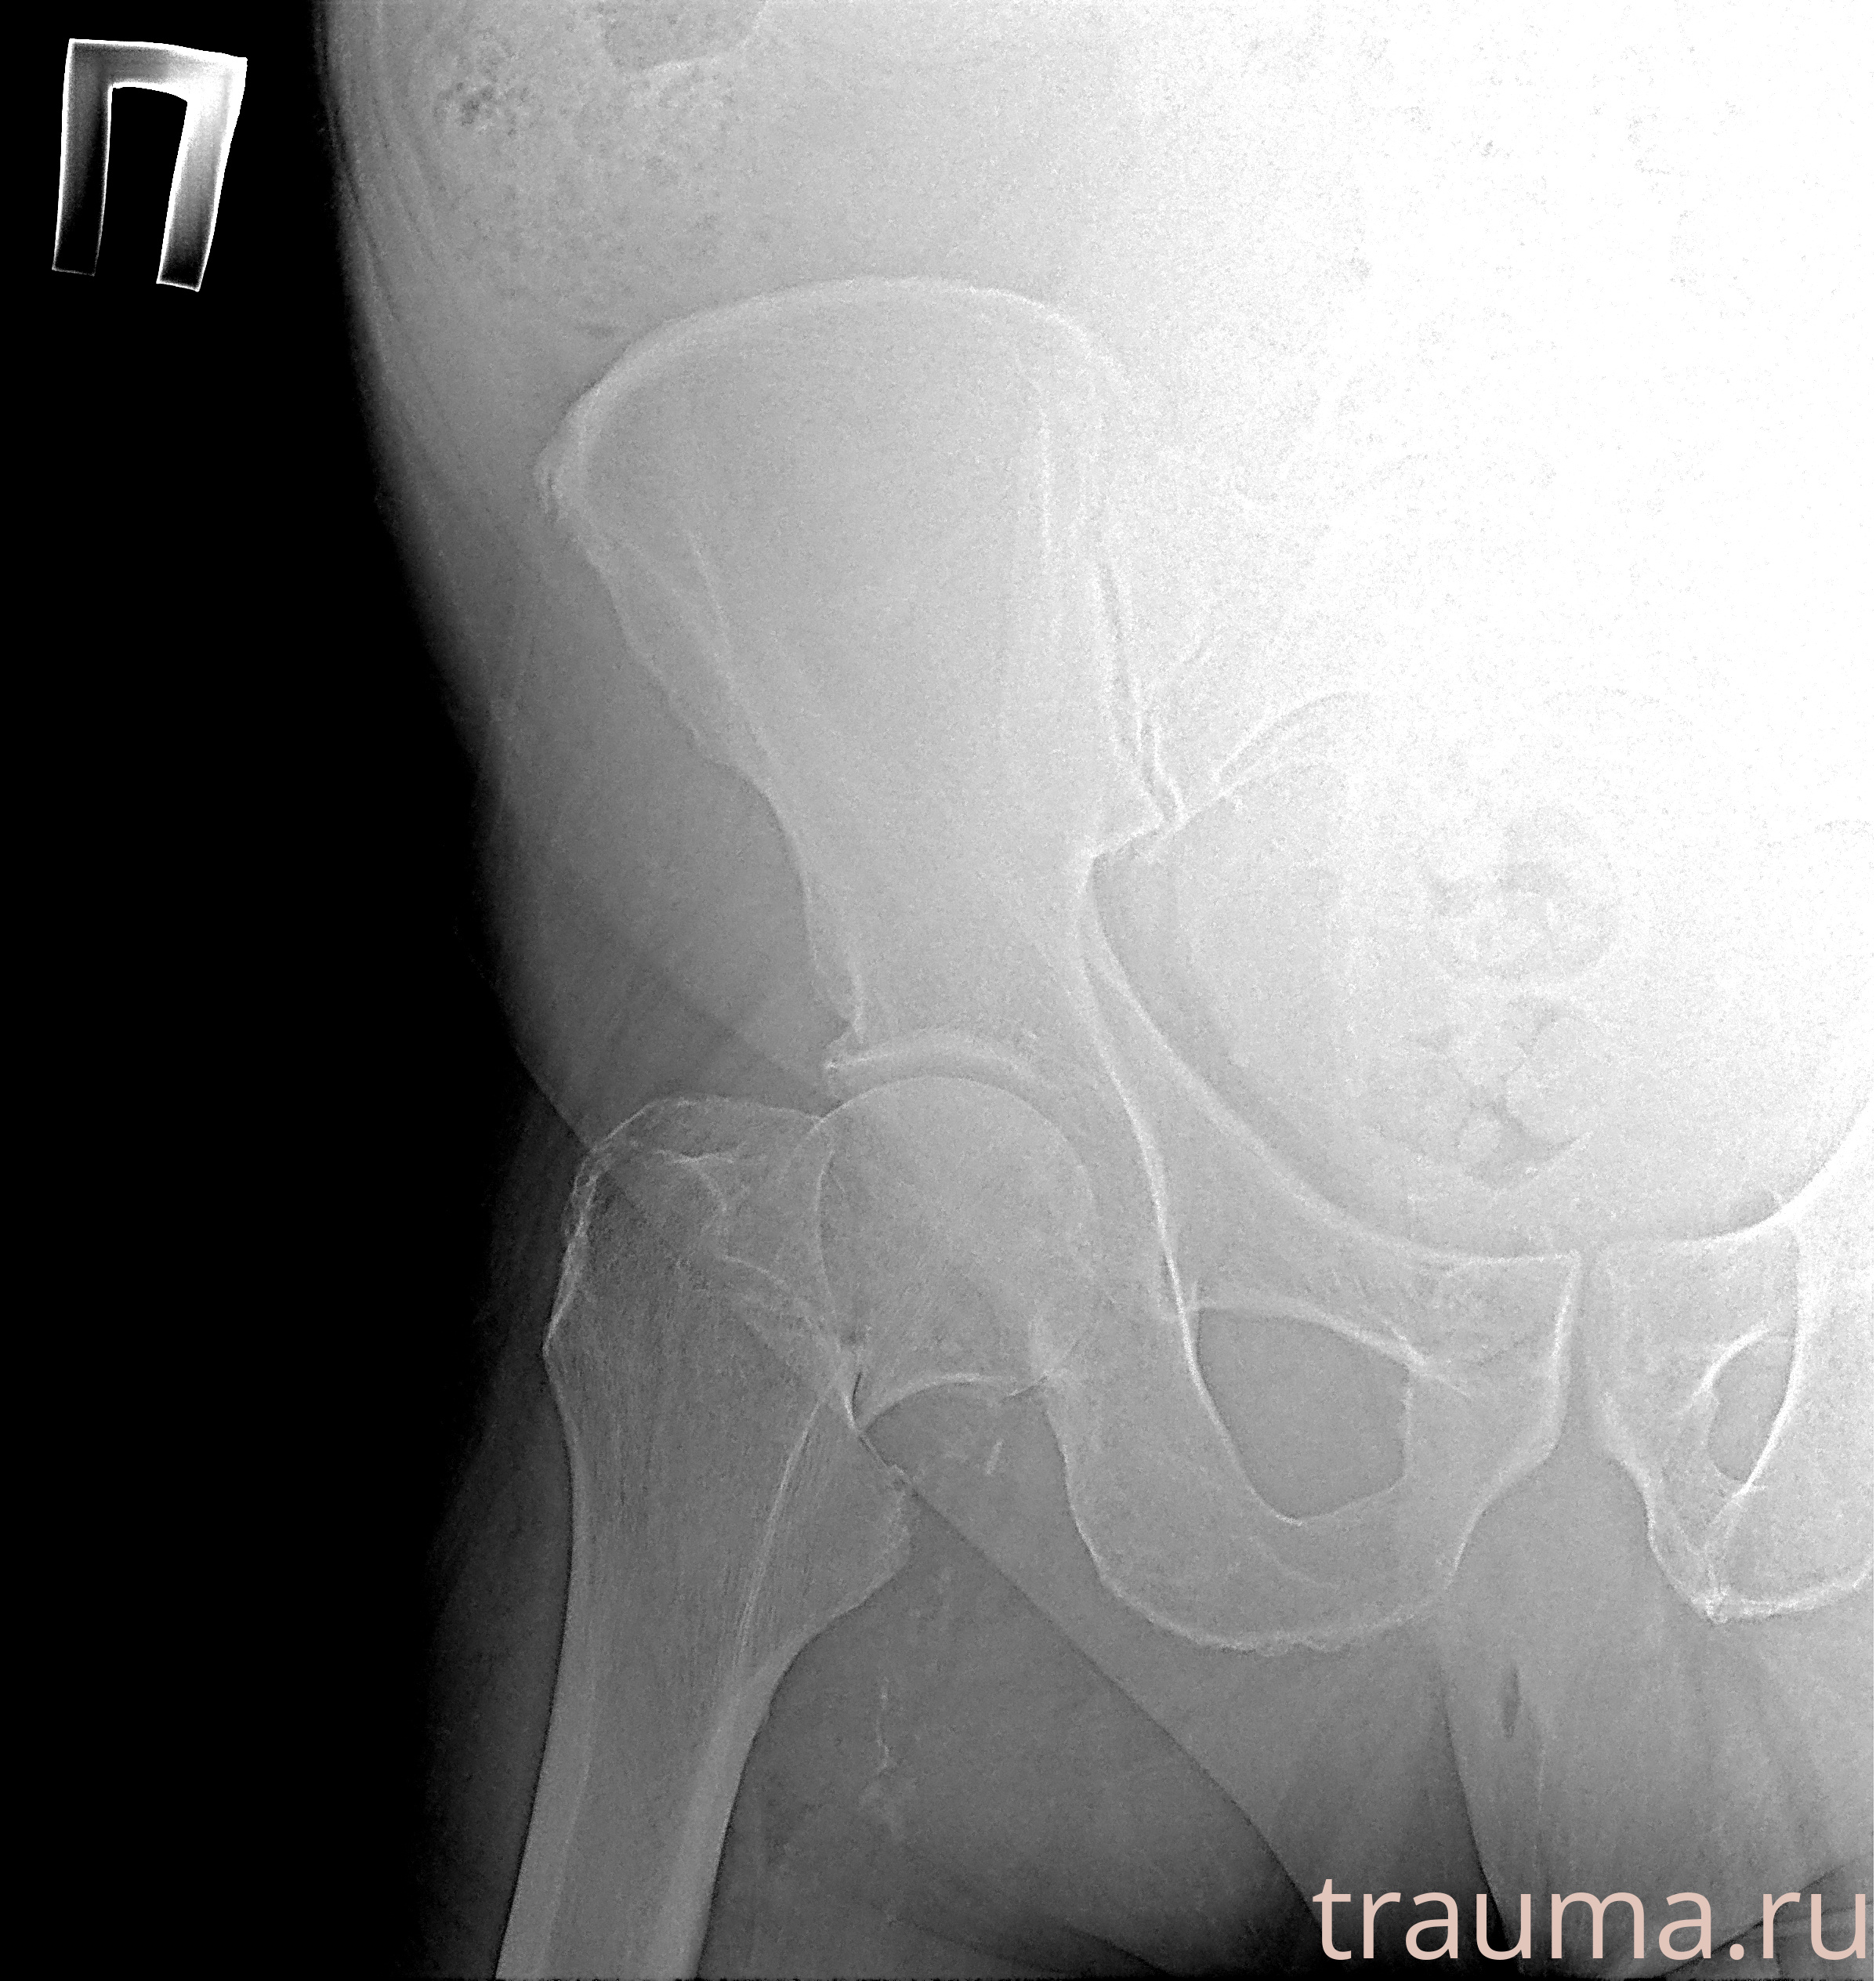

Рентгенограммы

Рентген на дому: по вашему адресу приезжает врач-рентгенолог, травматолог-ортопед с мобильным рентгеновским аппаратом, проводит диагностику травмы или заболевания, делает необходимые рентгенограммы, дает рекомендации по дальнейшему лечению. Получить качественные снимки в домашних условиях возможно благодаря уникальной методике, разработанной МосРентген Центром для института  Склифосовского